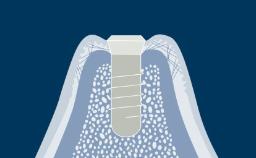

- identify specific indications where implants may assist in replacing missing teeth